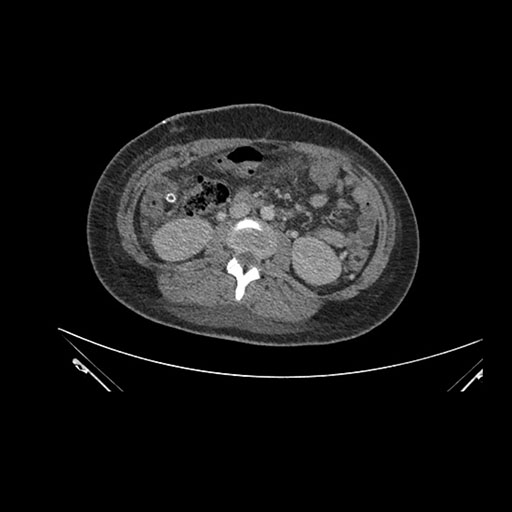

Imaging Analysis

Look through the patient's CT scan to identify any areas of concern for the necessary procedure.

Axial Arterial

Based on initial findings, which issue(s) would you be most concerned about?